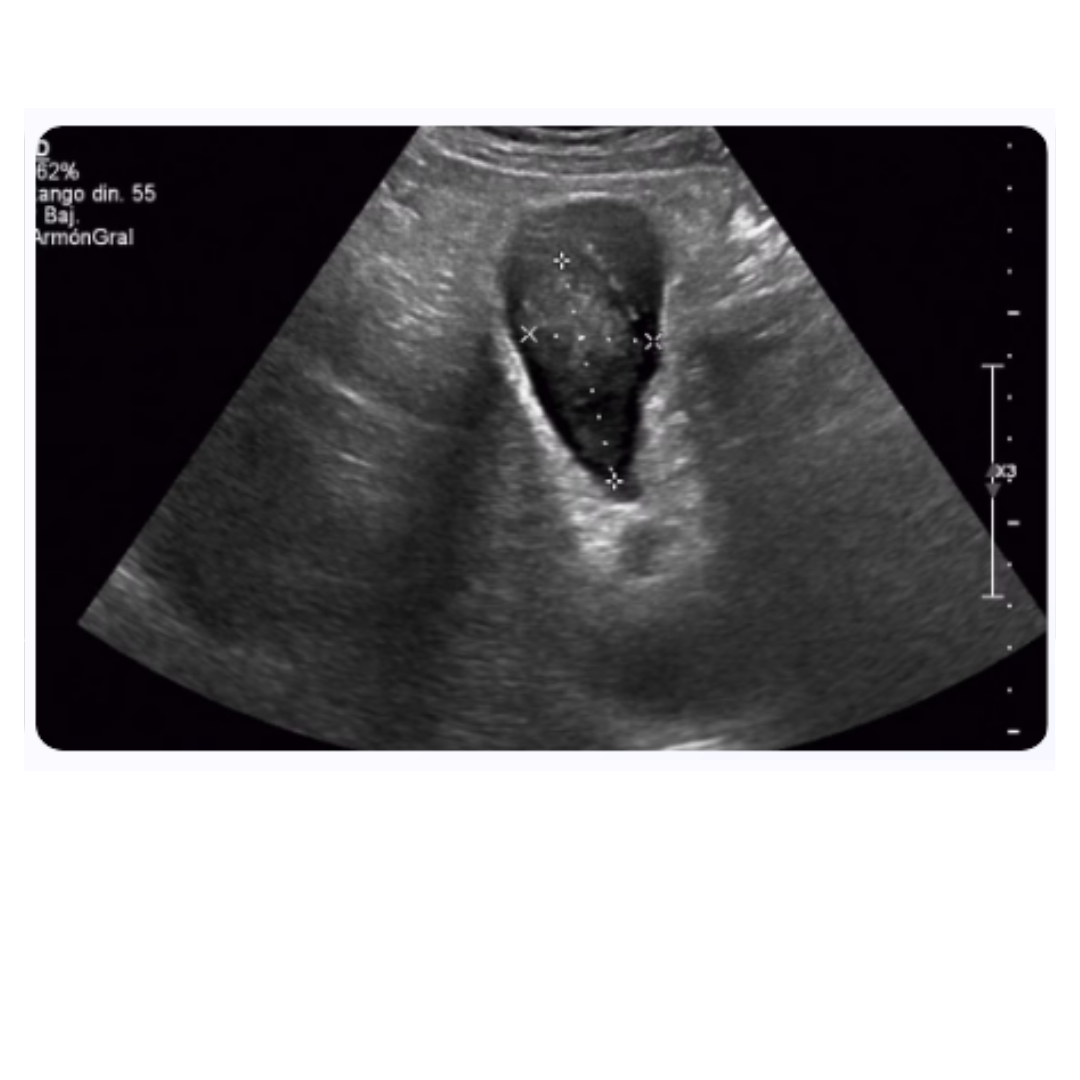

Ecografía doppler de órganos abdominales

La ecografía Doppler es otro método de imagen no invasivo, esencial para la evaluación de la arquitectura y la vascularización de los órganos abdominales en pacientes con LLA. Este procedimiento es significativamente útil para detectar esplenomegalia, hepatomegalia y alteraciones en los órganos que podrían sugerir infiltración leucémica o complicaciones secundarias a la enfermedad o su tratamiento.